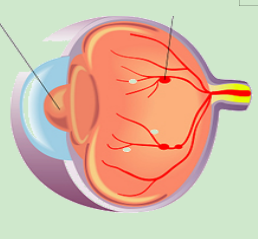

1.png

正常视网膜血管